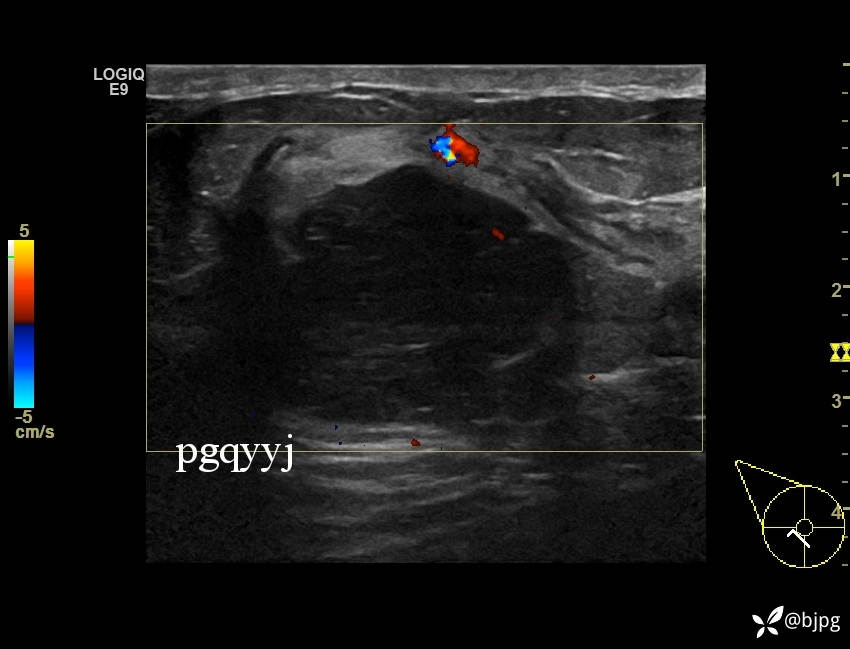

【患者信息】:女性36岁

【主诉】:发现右乳肿物一周

【检查】:超声

【临床诊断】:右乳结节,性质待定

【治疗经过及结果】:穿刺活检,欢迎同道讨论,穿刺病理数日后公布。

乳腺分叶状肿瘤 (7)